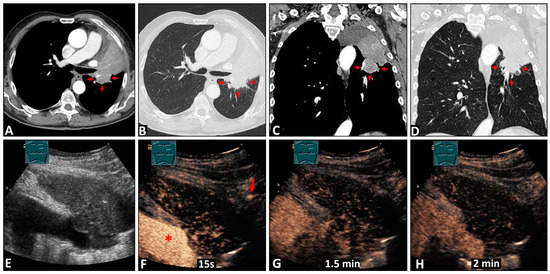

3.2.1. Differentiation between the Tumor and Atelectatic Tissue on B-US

3.3.1. Differentiation between the Tumor and Atelectatic Tissue on CEUS